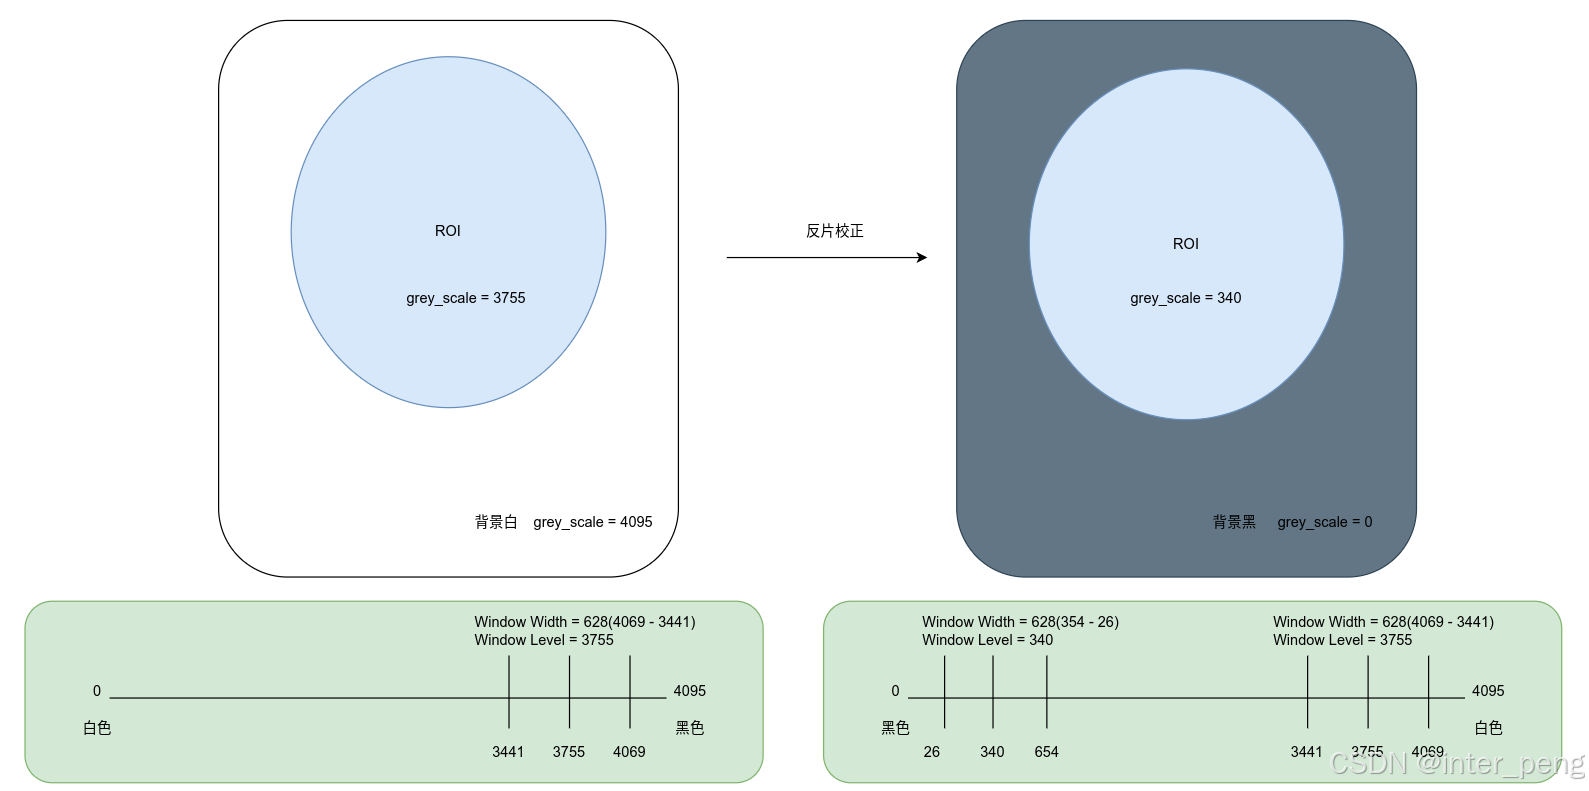

根据上面的示意图:

大概的原理就是:

1, 由于图像整个像素的灰度都发生了翻转. 比如原来的ROI(感兴趣区域)的灰度值, 正好和当前的WindowLevel/Center = 3755是一致的, 所以可以在反片中, 看到ROI区域;

2, 经过反片校正后, ROI区域的灰度值, 从原来的3755, 变成了4096 - 3755 = 340.

如果维持当前的窗宽窗位不变, 只能展现: 3441 ~ 4069这个灰度范围内的图像, 而ROI区域的灰度值是340, 小于这个下限, 所以小于3441的区域, 都会被置为黑色.

这就解释了, 为什么第一次反片校正后, 整个图像都是黑色的了.

3, 将WindowLevel/Center从原来的3755, 调整为4095 - 3755 = 340, 那么能够显示影像的灰度范围, 就变成了 26 ~ 654的灰度区域.

而ROI的灰度值为340, 正好落在了这个灰度范围内, 所以就可以看到了.